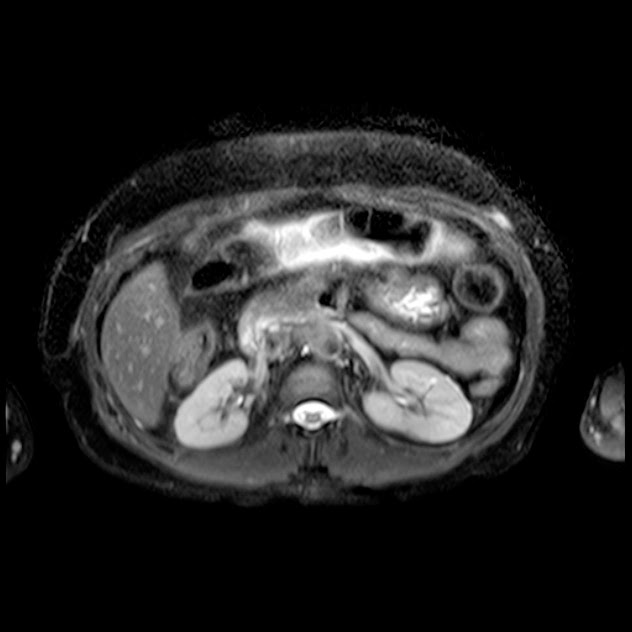

Caso interesante #5

Paciente con dolor en hipocondrio derecho.